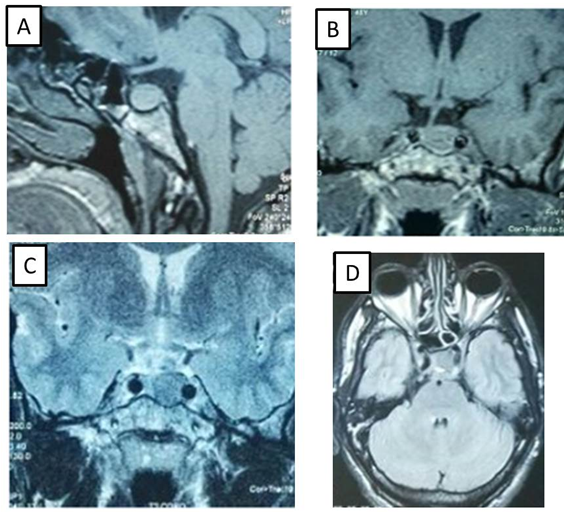

In March 2017, the patient was admitted and on the physical examination acromegaly was suspected because of typical acromegalic features (including acral overgrowth, excessive weating, headaches and deep voice). Acromegaly was confirmed by elevated IGF-1 : 679,9ng/mL (normal: 72-225ng/mL),basal levels of GH was not suppressed during the oral glucose tolerance test (OGTT test) and the complement by MRI showed the presence of a 12mm pituitary adenoma intensely intensifying after injection of Gadolinium (Figure 1). Other pituitary, thyroid hormone levels, and biochemical tests were within normal ranges except for hyperprolactinemia: 30, 42ng/mL (normal: 4,04 – 15,2ng/mL).

Figure 1 MRI images of pituitary macroadenoma.

1. Sagittal T1-weighted image,

2. Coronal T1-weighted image,

3. Coronal T2-weighted image,

4. Axial T2-weighted image.